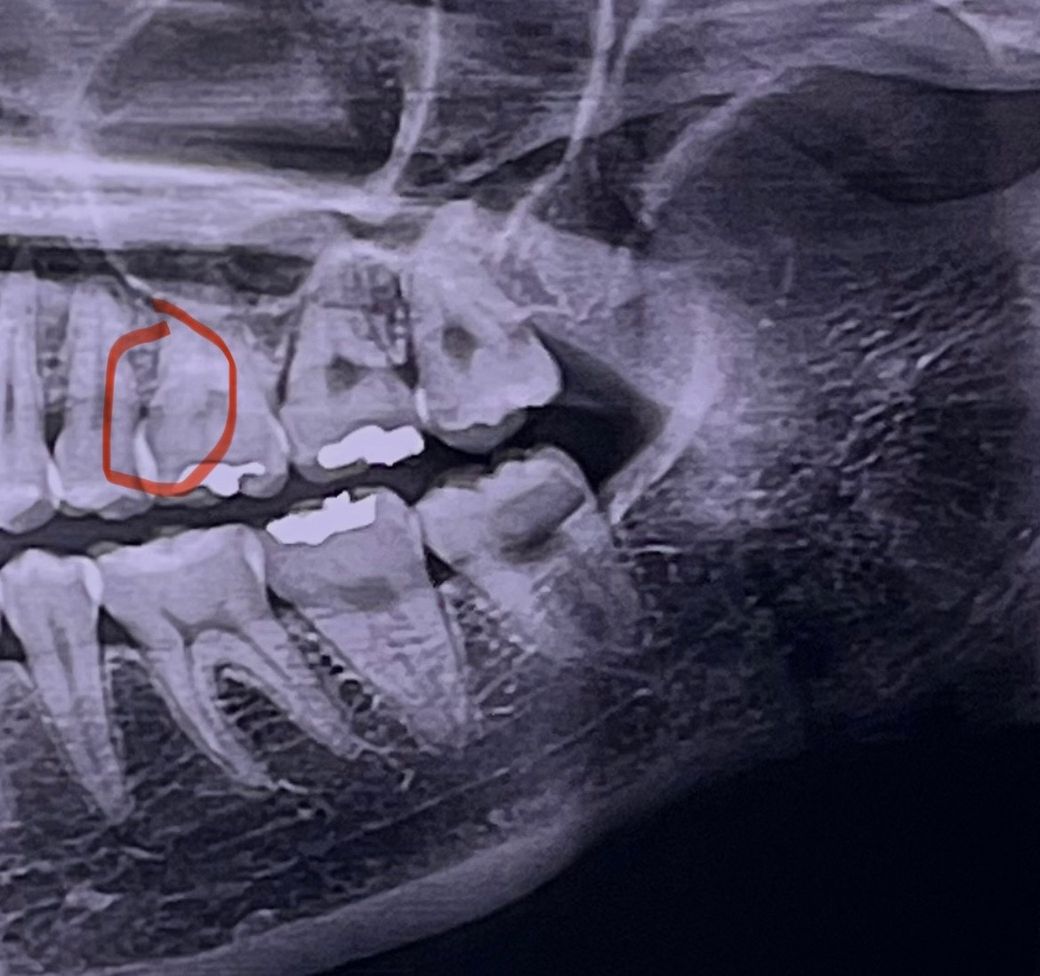

인접면 충치 생긴걸까요? 엑스레이 사진 첨부

동그라미 친 부분 엑스레이상으로 봤을때 충치가 발생한걸까요? 최근 치과 검진갔을때 엑스레이 찍긴 했는데 원장님께서 따로 엑스레이는 확인을 안하셨어서 궁금합니자.

치아가 겹쳐 보여서 파노라마 사진으로는 확인이 어렵고 작은 엑스레이를 다시 찍어보셔야될것같습니다.

옆 작은 어금니와 중첩되어 판독이 좀 어렵긴 한데 일단은 옆면 충치가 의심되긴 합니다 치근단 엑스레이 한번 더 찍어보면 좋을 것 같습니다